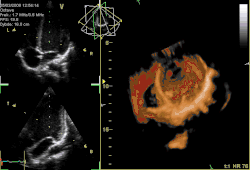

Obecnie istnieje wiele zastosowań i odmian badania ultrasonograficznego, m.in. możliwość przedstawienia wyniku badania USG w trójwymiarze poprzez połączenie kilku sekwencji obrazów. Jednym z zastosowań USG jest USG dopplerowskie.

Obecnie wykorzystanie rezonansu magnetycznego jest coraz powszechniejsze w praktyce klinicznej. W ostatnim dziesięcioleciu jakość obrazu otrzymywanego w czasie badania uległa znaczącej poprawie, dzięki czemu rezonans magnetyczny stał się doskonałym uzupełnieniem diagnostyki w wielu dziedzinach medycyny. Zastosowania MRI stały się metodą z wyboru w nieinwazyjnej diagnostyce obrazowej nie tylko serca[6].